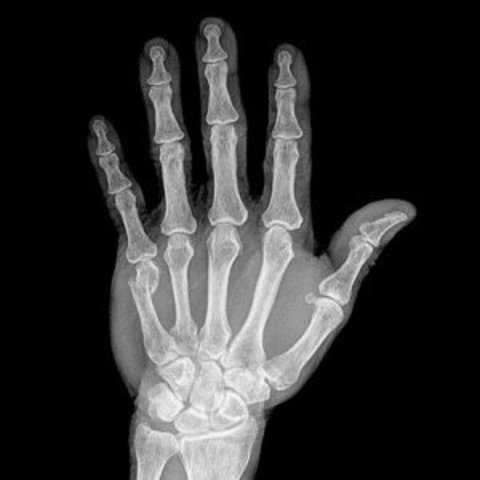

• X-Ray

X-Ray

Before X-Ray machines were invented broken bones were all diagnosed by physical examination and a doctor guessing the location. The X-Ray was accidently discovered by Wilhelm Conrad Röntgen in 1895 he was studying cathode rays during 1895, before he discovered X-rays.